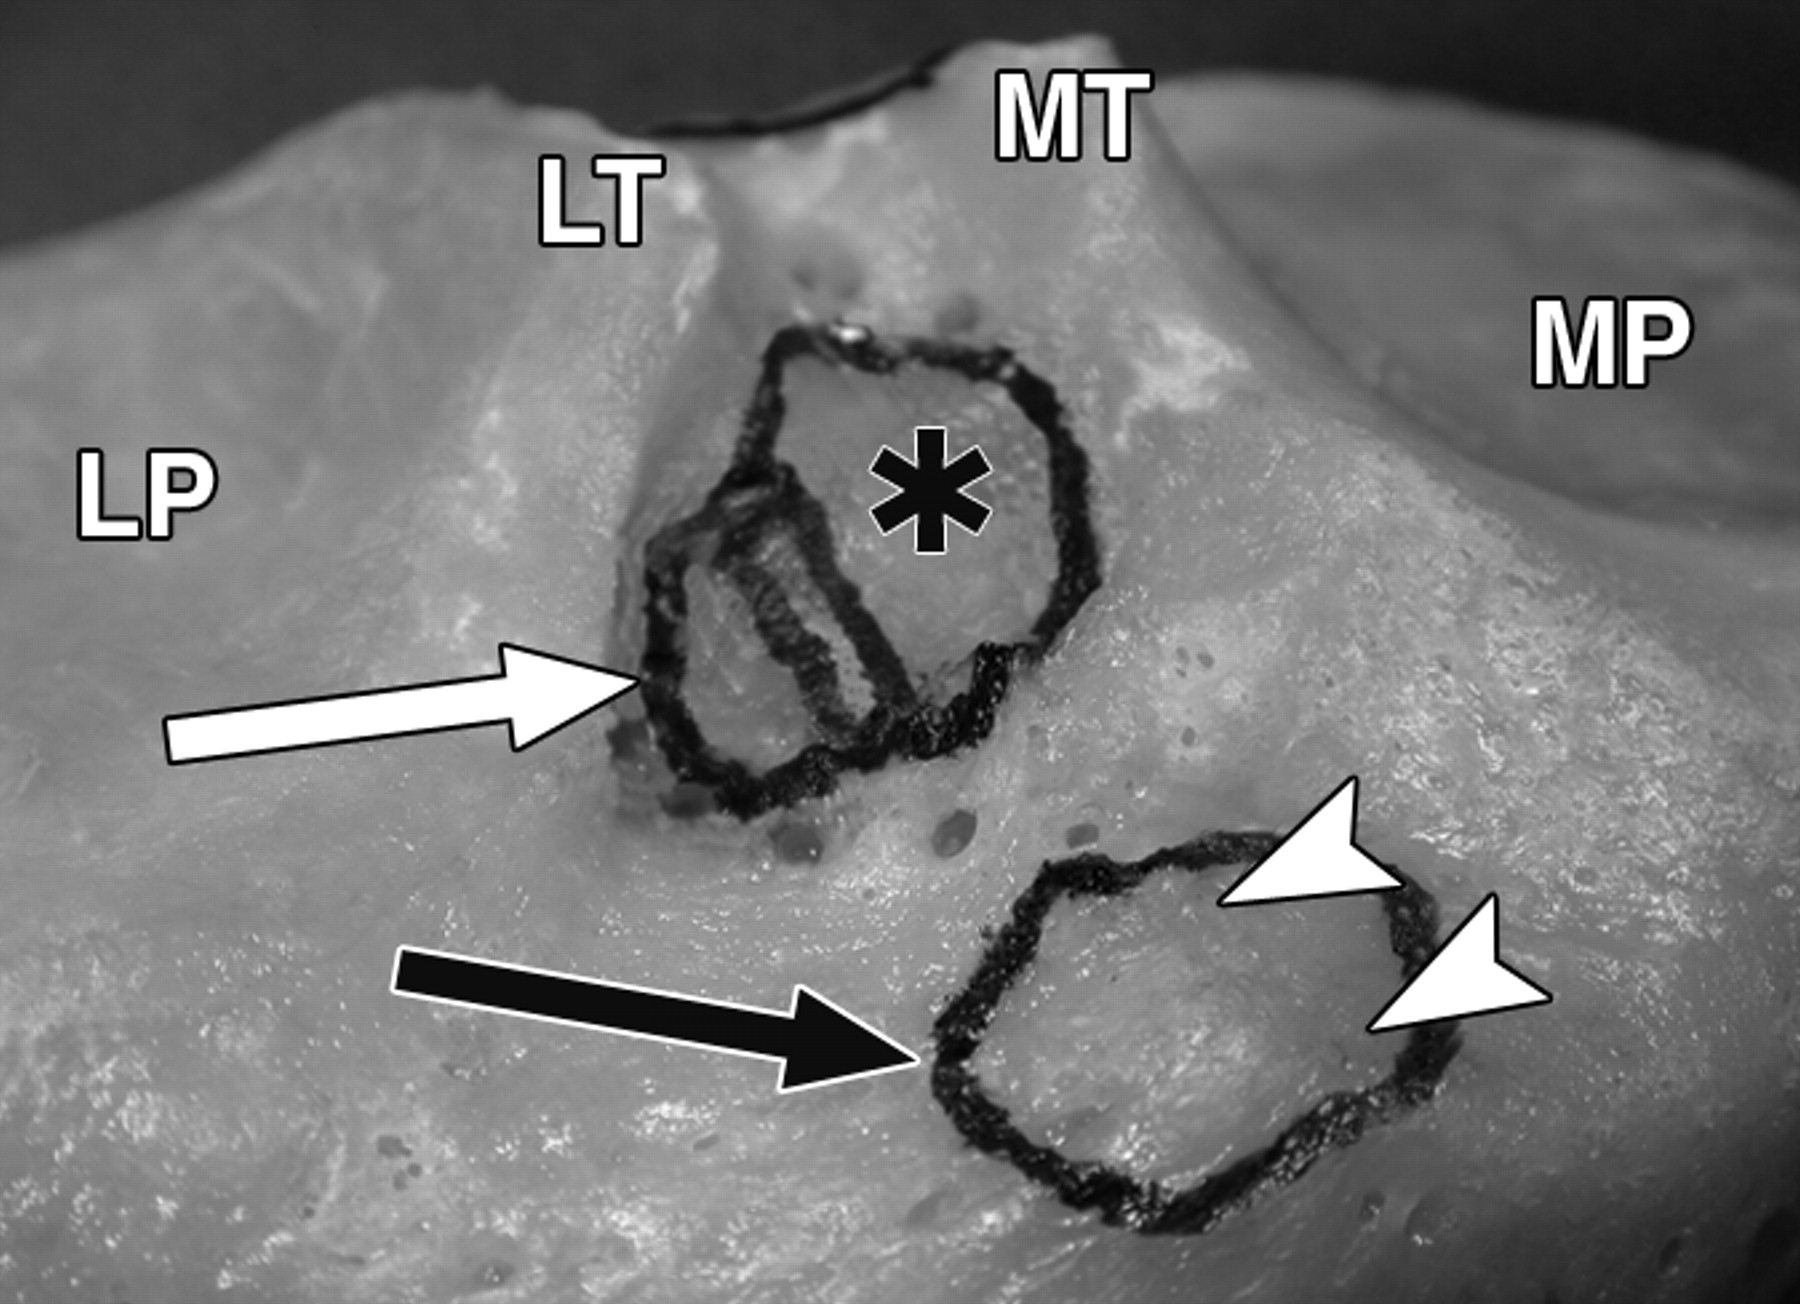

图1D-59岁男性大体标本。

黑色长箭头表示内侧半月板(MM)前根;黑色短箭头表示内侧半月板后根;白色长箭头表示外侧半月板(LM)前根;白色短箭头表示外侧半月板后根。照片对应于C。MP =内侧胫骨平台,MT =内侧胫骨结节,LT =外侧胫骨结节,LP =外侧胫骨平台。P =后交叉韧带。